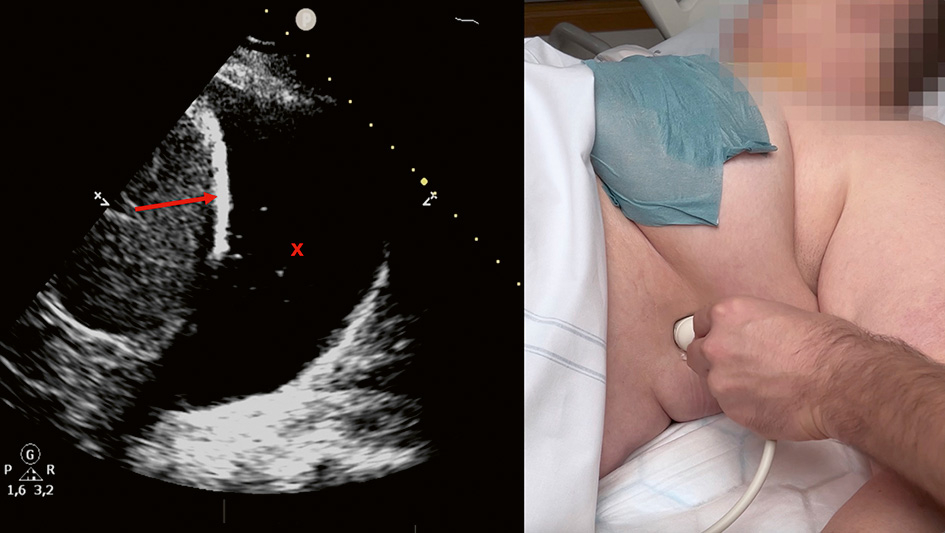

C. Under direktvisualisering (»in plane«-teknik) används först en 21G 80 mm nål för att bedöva tänkt stickkanal. I samma stickkanal införs sedan under direktvisualisering den ihåliga 18G-nålen varigenom Seldinger-ledaren matas in. I bilden ses nålspetsen (pil) som ligger i den blodiga pleuravätskan. Stickriktningen är mot diafragma, vilket är att föredra vid Seldinger-teknik eftersom dränet då oftast hamnar precis ovan diafragma. Om sticket görs från vänster i bilden förs den ihåliga ledarnålen och Seldinger-­ledaren in mot den sköra och rörliga lungan i stället för att studsa mot den mer robusta diafragmamuskulaturen.

D. Ultraljudsproben lämnas på plats till dess att Seldinger-­ledaren har införts. Då bekräftas visuellt att ledaren (pil) har hamnat i pleurarummet.